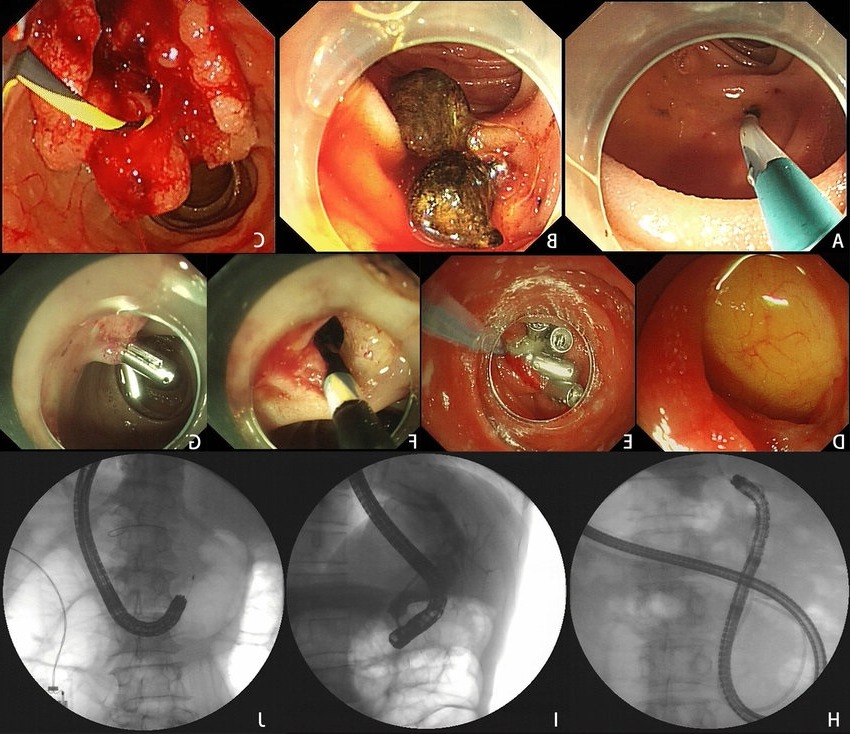

از مهمترین محورهای آموزشی این مرکز میتوان به آموزش عملی روشهای اندوسکوپی پیشرفته شامل EUS، ERCP و ESD اشاره کرد که از ویژگیهای متمایز برنامههای فوقتخصصی در این مرکز محسوب میشود:

ERCP یکی از روشهای کلیدی در درمان اختلالات مجاری صفراوی و پانکراسی است. در این مرکز، پزشکان در محیط بالینی مجهز و با راهنمایی گامبهگام اساتید متخصص، مهارتهای مورد نیاز برای انجام اسفنکتروتومی، خارجسازی سنگها، استنتگذاری و رفع تنگیهای مجاری صفراوی را بهصورت عملی فرا میگیرند.

این تکنیک پیشرفته جهت برداشت کامل ضایعات پیشسرطانی یا بدخیم اولیه از دستگاه گوارش، در مرکز بهصورت ساختارمند آموزش داده میشود. آموزش ESD شامل اصول انتخاب بیمار، شناخت ابزارهای اختصاصی، مراحل گامبهگام عمل و مدیریت عوارض احتمالی است. این دورهها از جمله معدود برنامههای آموزشی در کشور هستند که امکان تمرین عملی این تکنیک پیچیده را برای پزشکان فوقتخصص فراهم میسازند.